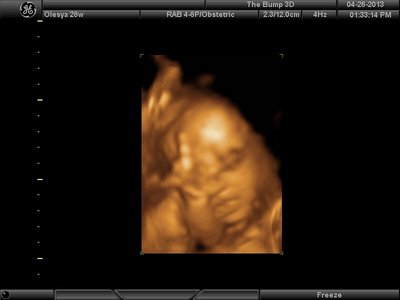

А я вчера на 3Д УЗИ ходила. Моя звезда закрывалась в еми 4мя конечностями. Просто пополам сложилась и спала себе сладко. УЗИстка провела со мной час, кое-как расшевелили маленькую, но ручка была постоянно на мордашке и засыпала она почти сразу снова. Я и на мяче прыгала и живот трясла. В конце более-менее фото вышли, но качество меня не порадовало. Возможно фри оф чардж еще раз переделают. Со средней фотки были отличного качества, а эти сплошное разочарование. Вот тут что-то более-менее еще. Главное пальчик оттопырила так смешно, мол минуточку. Вообще немного жутковатые фотки..хаха

Вложения: |

image.jpg [ 47.86 КБ | Просмотров: 1177 ]

Еще одна, качество ужасное..

image.jpg [ 60.32 КБ | Просмотров: 1174 ]

Губёшки и лоб - твои! Носик, вроде, папин . Вообще, кажется, на младшенькую похожа! Мы тоже губошлёпы ещё те , фотки правда тоже не оч получились, я только парочку сохранила

katerina73 писал(а): Вот, пожалуй, самая лучшая фотография. Катюш, так ваш пупсик зато отлично виден, черты лица отменно видны. Те первые две вчерашние, вторые средней дочки. Со средней черты отлично видны, с этой куклой не понятно..

Почему говорите качество плохое? По моему очень даже ничего, все хорошо видно.

Ой, Ксюнь, класс!!! Я говорю у вас у всех очертания носика, губок видны отлично...у моей же все размыто как-то и везде разное. На одной фотке вообще не нос а аэродром. Я ничего не поняла. Но УЗИстка сказала что она очень близко к плаценте мордашкой была поэтому так мутно все. Я надеюсь они мне переделают бесплатно все же. Я бы очень хотела. Так рассмотреть охото как следует, за это ведь и платила как никак..:-)

Олеся ну красотка у тебя!! слушай еще один губастик будет  по моему ты зря, очен прилично лицо видно девочки у всех такие сладкие они на этих фотках

Анют, зай, это я приличные самые выставила...на других вообще нечто...меня переносица смутила с носом, хочу пересмотреть..